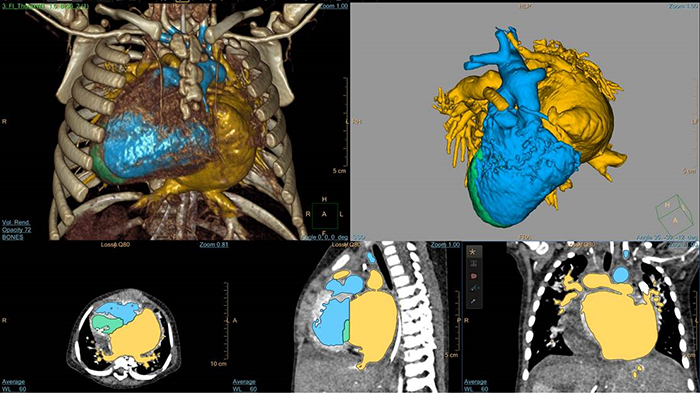

3D Modeling com IntelliSpace Portal

Segmentação do modelo cardíaco EchoNavigator